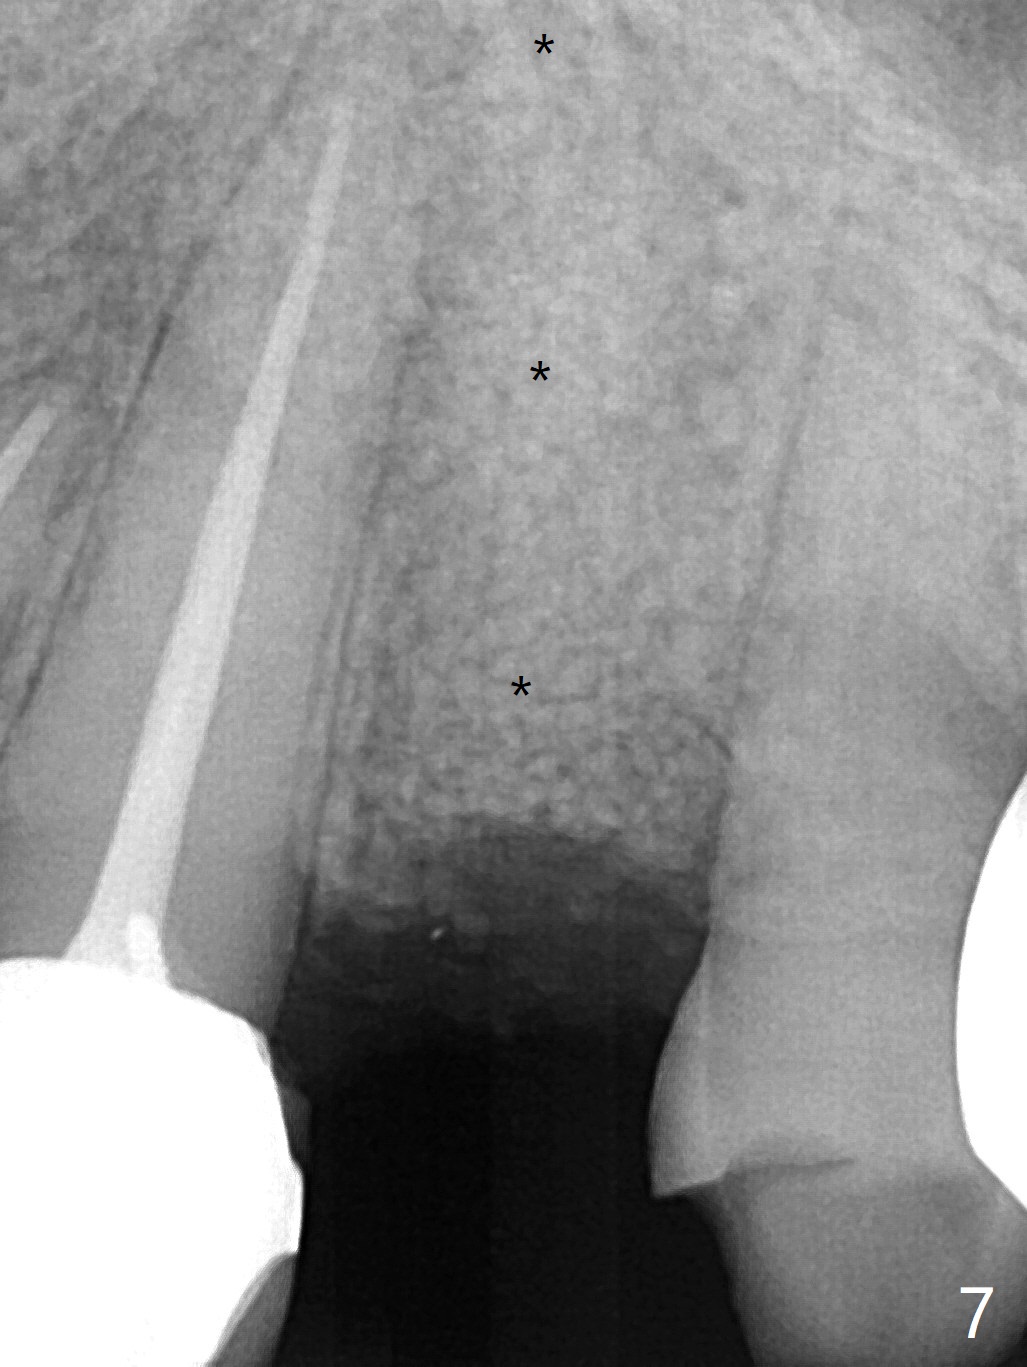

68岁女左上4颊侧瘘道(图一:*),与根尖颊侧骨板缺失相通,其实腭侧根尖周围病变更大(也与颊侧窝相通),术中没有注意腭侧根接近3(图二:P),稀里糊涂的基本顺着腭侧根(颊侧)走向钻洞(图四,与图三理想方向对比),突然记起术前设计钻洞必须在腭侧牙槽窝远中颊侧,在远中建立新洞眼(图五),之后无法再次建立新洞眼,只好利用同一个侧面切割钻头将钻洞往远中移位,同样效果不佳(图六),最后只好放弃,放置粘性骨粉(图七:*),覆盖PRF膜,6个月胶原膜,PGA缝线,牙周胶水。术后重新分析表明顺着腭侧牙槽窝种植与尖牙还是有分离(图八,九:*),因为牙槽窝是斜型的(图十:黑色),不过离颊侧骨板也接近(图八:B)。所以钻洞必须斜型针对远中骨壁,表浅些(图十一:红色箭头);一旦进入骨板,改变角度(图十二:红色箭头),适当矫枉过正,随着植体增大,钻洞会往近中偏移(白色箭头)。最好植体方向理想(图十三)。不过植骨后钻洞偏移可能性比较少。缝线和牙周胶水似乎是一个稳妥固定胶原膜方法。术后病人抱怨水肿严重,术后八天颊侧根尖隆起是由于骨粉推出骨板之外(图十五,十六:*),上颌窦底板无意穿孔(^)伴有上颌窦膜(M)增厚,与术前对比(图十七:上颌窦窦腔清晰)。术后一个月6个月吸收膜不见了,大多数缝线已经脱落,最后两根缝线撤除后,牙槽窝开口已经关闭,好像主要成分是骨粉(图十八)。术后5个月牙槽嵴宽,角化龈也宽,好像可以植入4x11.5毫米植体(图十九)。